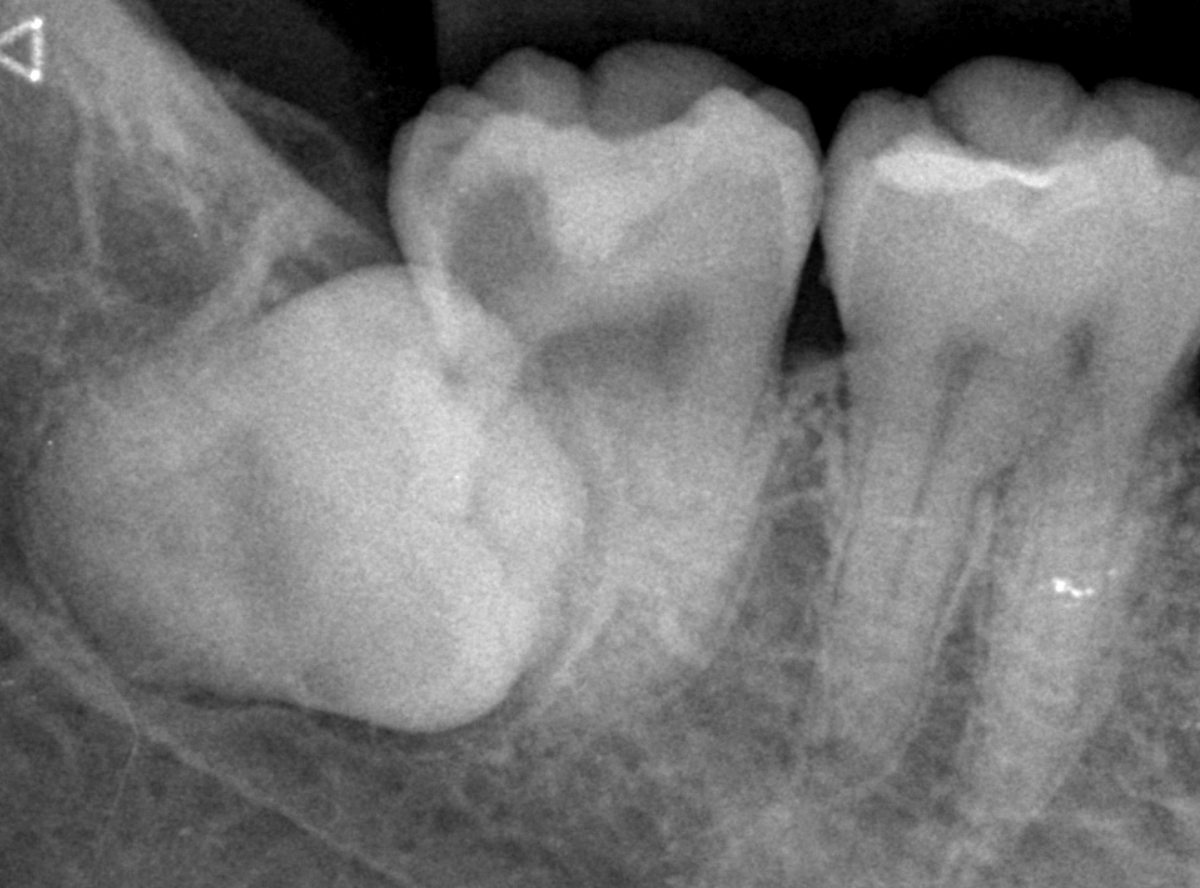

Case.9 レジンの中で大きく広がった虫歯

他の歯の治療希望で来院された患者さんです。

検査をすると、他の場所にも大きな虫歯が見つかりました。

レジン(つめもの)の下の虫歯で、この写真では、わかりづらいですが、中で広がっています。

レントゲン写真で確認します。

レジンの下が虫歯になっているのが確認できます。

まず、手前の歯から治療をします。

つめものを外すと、大きな虫歯が出てきました。

慎重に虫歯を除去します。

かなり虫歯が進行しています。

後ろの歯の治療も進めます。

全ての虫歯を除去したところです。

かなり広範囲な虫歯になっていました 。

このように一度治療した箇所は虫歯の再発しやすい部分でもあります。

特に隣の歯との間のレジンの中は虫歯が見つかる事が多いです。

自覚症状がなくても、定期的なメンテナンスとレントゲン写真での確認をおすすめします。